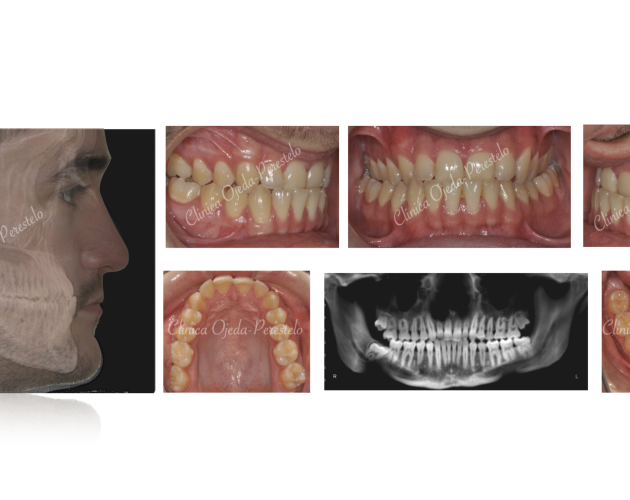

Clase II esquelética con Cirugía de Avance Md Casos de Éxito - Ortodoncia Plástica (Invisalign/Angel) - Adultos